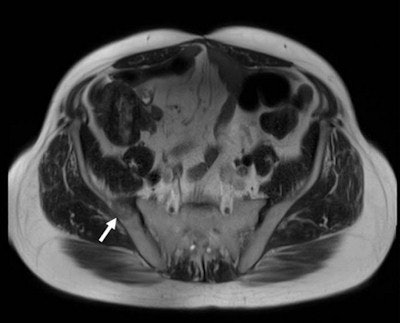

Some methods allow totally noninvasive treatment. This is the latest trend: intervention without needles or catheters in, for instance, the treatment of uterine fibroids. These benign uterine tumors can be treated with focused ultrasound (FUS). The ultrasound waves are concentrated to produce heat within a focal point. To treat uterine fibroids, the ultrasound waves are applied via an ultrasound source in the MRI table, MRI being used as an imaging procedure to locate the fibroids and to measure the development of the temperature within the fibroid and surrounding tissues during treatment.